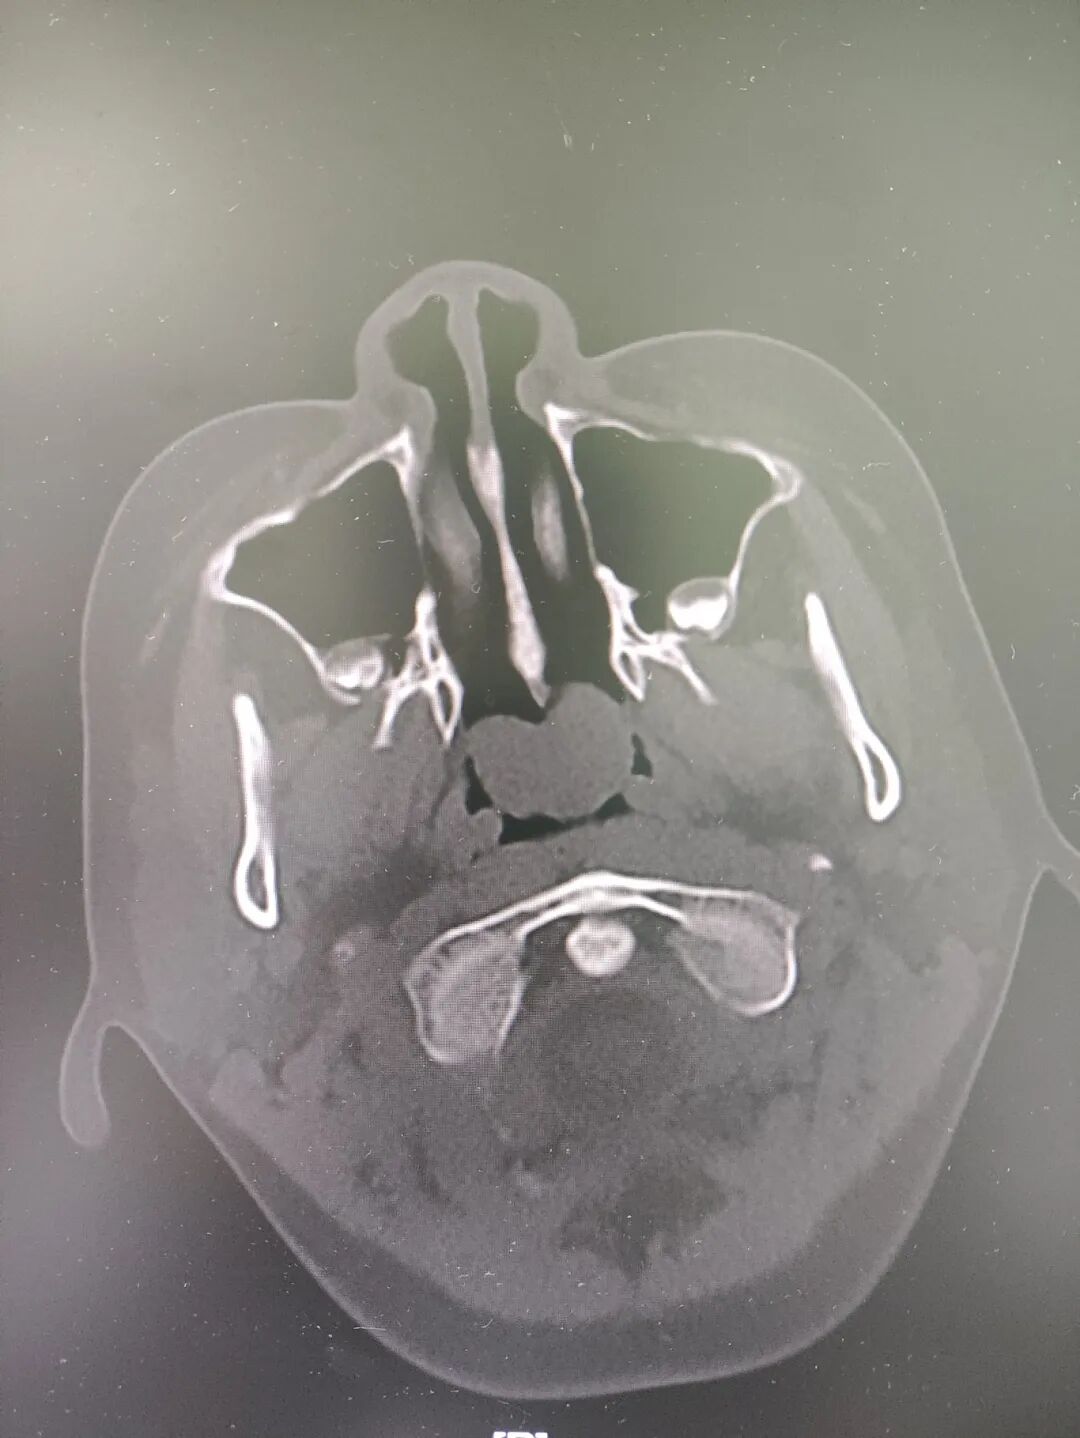

耳鼻喉科接诊医生查体发现,可可的鼻塞不伴随打喷嚏和流鼻涕。进一步详细检查,结果显示,可可的左侧鼻腔后端有一处直径近2厘米的肿物。肿物不仅堵塞了后鼻孔及鼻咽部,还阻碍了鼻窦的引流,引起了鼻窦炎。

术后的病理检测结果显示切除的肿物为良性(鼻息肉)。家长悬着的心终于放下了。

鼻息肉是一种常见的鼻部慢性疾病,外观上像新鲜荔枝,表现为一个或多个表面光滑、触之柔软、半透明的肿物,可以出现在鼻腔和鼻窦黏膜的任何部位。鼻息肉常表现为持续性鼻塞并呈进行性加重,甚至完全阻塞鼻腔通气,鼻塞严重者表现为闭塞性鼻音、睡眠打鼾、分泌物增多、嗅觉减退或丧失。一旦治疗不及时,就会导致病情加重,鼻息肉越长越大,直至填满整个鼻腔,最终导致鼻子变形,鼻背变宽,形成了外观酷似青蛙的鼻子——“蛙鼻”。